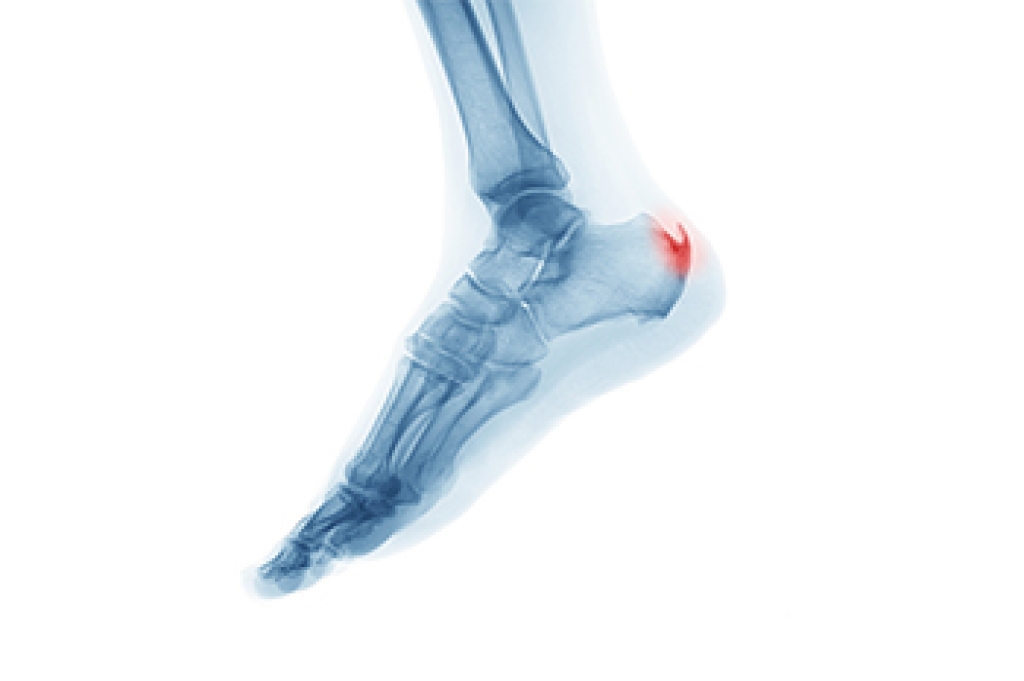

Heel spurs, a common foot condition, refer to calcium deposits that develop on the underside of the heel bone. They often form in response to repetitive stress or strain on the foot's ligaments and muscles. While heel spurs themselves may not cause pain, they can contribute to discomfort and inflammation in the surrounding tissues, leading to conditions such as plantar fasciitis or Achilles tendonitis. Heel spurs typically occur in the area where the plantar fascia, a thick band of tissue that runs along the bottom of the foot, attaches to the heel bone. As the body attempts to heal and repair the damaged tissues, calcium deposits may accumulate over time, resulting in the formation of a bony protrusion. Understanding the location and nature of heel spurs is essential for effective treatment and management strategies. If you have heel pain, it is strongly suggested that you consult a podiatrist who can accurately diagnose heel spurs and offer you appropriate treatment methods.

Heel spurs are formed by calcium deposits on the back of the foot where the heel is. This can also be caused by small fragments of bone breaking off one section of the foot, attaching onto the back of the foot. Heel spurs can also be bone growth on the back of the foot and may grow in the direction of the arch of the foot.